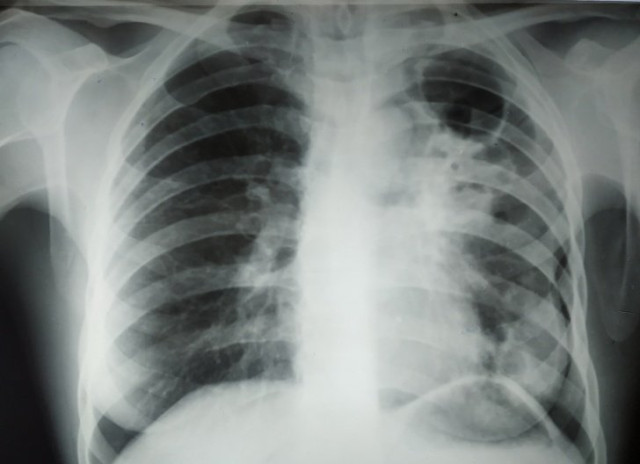

Збудник туберкульозу буде знищувати сам себе

Незважаючи на те що в розвинених країнах сьогодні туберкульоз зустрічається вкрай рідко, тільки в 2017 році в світі від нього померло близько 1,3 млн осіб. На даний момент хвороба вважається невиліковною, оскільки викликає її бактерія Mycobacterium tuberculosis (паличка Коха) здатна пристосовуватися до антибіотиків. Однак на початку 2019 року вчені розповіли про токсин MbcT, здатний вбивати бактерії, який, до речі, самі бактерії і виробляють. В результаті дослідження, проведеного на мишах, заражених Mycobacterium tuberculosis, з’ясувалося, що MbcT здатний знищувати велику частину паличок Коха і збільшувати виживаність хворих.